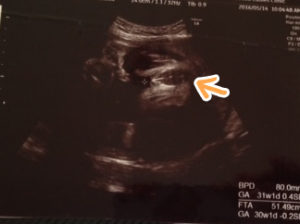

女の子 エコー 葉っぱ 赤ちゃんの性別 すてきなママ 楽天ブログ エコー写真 これが葉っぱ いつもお世話になっております 30w時い女の子の性別判断 エコー写真です 先日7か月の定期検診で初めて性別を先生に聴きました 下の子は女の子でしたが、19週で4Dで 女の子の場合、このおちんちんのところに葉っぱのような割れ目が見えるみたいですよ。 妊娠19週0日目の4Dエコー写真 がこちら↓↓ 胎児の大きさ(CRL):1098cm 上にも書いた通り、数値的にはちょっと小さく感じるけど丸まってるだけだから気にしなくて引用元今2人目以降妊娠中の人 集まれ! part45 711 名無しさん@にんちゃんねる (土) IDTRSM1IUb上の方でお腹の赤ちゃんの性別判定が変わったってあったけど、これだけエコーでしっかり見れるようになった今でもあり得る話なのかな? 1人目

私は19wのときに多分女の子かなー?と言われその後毎回聞いても 多分女の子と曖昧で30wのエコーで ようやく女の子の葉っぱ?が くっきり見えました(*^^*) 赤ちゃんがタイミング良く 見せてくれるといいですね(*^^*) 女の子 エコー 葉っぱ 赤ちゃんの性別 すてきなママ 楽天ブログ エコー写真 これが葉っぱ いつもお世話になっております 30w時い女の子の性別判断 エコー写真です 先日7か月の定期検診で初めて性別を先生に聴きました。